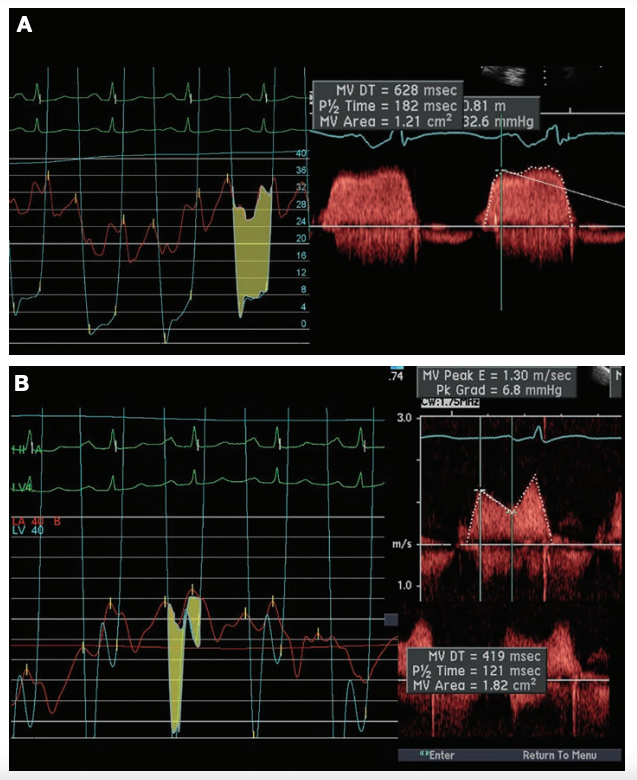

In general, the stenotic mitral valve area (MVA) can be measured in several ways (Figure 2).6 With confidence in the echocardiographic data, patients may be suitable for balloon valvuloplasty to open the stenotic valve and permit adequate cardiac output, and keep pulmonary hypertension at bay. At times, with equivocal data, exercise hemodynamics in the cath lab may be necessary. For best pressure and gradient data, use direct LA pressure from a transseptal approach rather than the pulmonary capillary wedge pressure (Figure 3). However, when pulmonary capillary wedge pressure is low and normal, it provides an effective first-line tool to screen for significant mitral valve gradients.

PBMV results in a gradient decrease of 50% or more, and a valve area increase to 1.5 cm2, the definition of success in the majority of the literature. In ideal valve anatomy, the mitral valve area will typically increase to 1.8 cm2 or more. Examples of the hemodynamic changes occurring in the pressure wave forms for a patient with MS before and after mitral balloon valvuloplasty are shown on Figure 4.

Figure 5 demonstrates the results of PBMV in young patient with low Wilkins scores with reduction of the mitral gradient after a single balloon inflation.

Although occasionally seen, caution in achieving complete resolution of a residual gradient should be used to avoid producing severe mitral insufficiency. In fact, the absence of a gradient after PBMV more commonly correlates with severe mitral insufficiency. The hemodynamics of this example suggest a competent valve; in fact, no mitral regurgitation was detected by echocardiography. It is worth noting that there is often a characteristic minimal peri-commissural leak seen with successful PBMV.